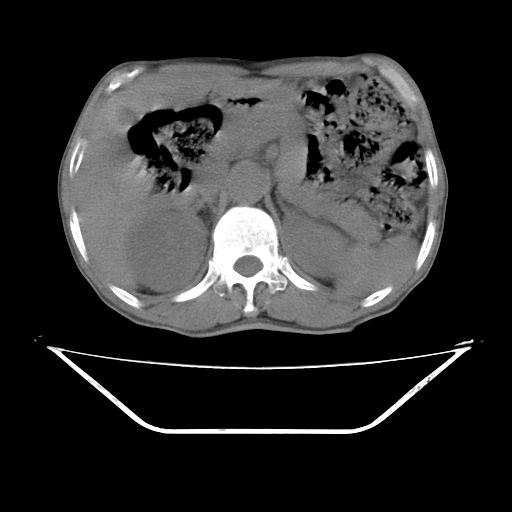

平扫

考虑右侧肾盂癌。右侧输尿管扩张未扫描完。

右肾盂癌,肾动脉受侵,右肾盂输尿管积水,管壁增厚,考虑种植转移

右肾盂移行细胞癌并右输尿管中段转移.肾积水.

3.右侧上段输尿管扩张,原因:(1)积水所致;(2)种植。